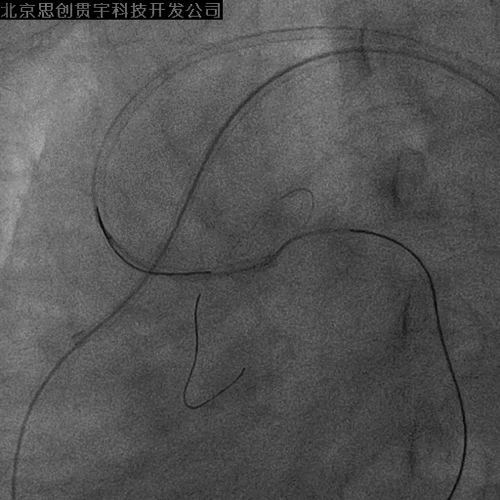

LCX-逆向PCI

PL-左房支-LCX侧枝

Corsair+SION

IVUS引导下UB3+corsair微导管进入正向指引

穿微导管技术送LCX导丝( Modified Rendezvous )

LCX-IVUS

LCX远端真腔,近端内膜下